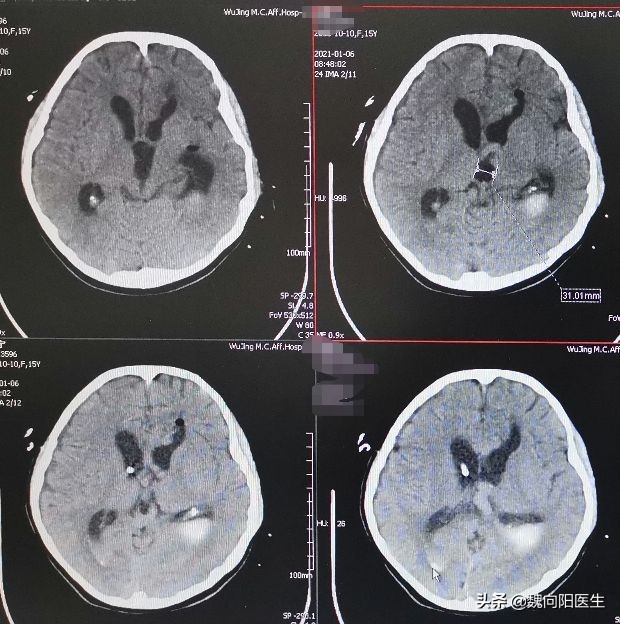

半个月之前科室收治了一名双侧侧脑室出血的15岁小姑娘, 她辗转多地来到我们医院就诊。

由于双侧侧脑室出血严重影响到意识水平,在头上打了三次眼儿放血,腰椎部还放了两次管子放血,持续两周多才把血基本上引流完毕。

赶紧给小姑娘安排淘CT检查,果不其然,小姑娘的脑室明显增大,脑积水了。